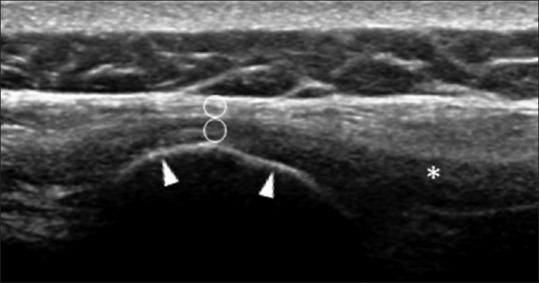

Enthesopathy is a main characteristic of ankylosing spondylitis (AS). However, ultrasonographic features of supraspinous enthesis in AS have not yet been reported.

Forty-seven AS patients and 22 healthy individuals were enrolled and completed the study. L4 supraspinous entheses were assessed through an ultrasound (US) unit with the participants in a lateral decubitus position. Entheseal echogenicity was interpreted upon inspection of the US image. An entheseal grayscale (GS) value determination, along with an echotexture analysis using a gray-level co-occurrence matrix algorithm, was performed. The thoracolumbar fascia just above the enthesis was also analyzed. An enthesis-to-fascia ratio (EFR) of each texture feature was used for the purpose of intergroup comparison.

The prevalence of abnormal entheseal echogenicity in the AS and healthy groups was 19.1% and 13.6%, respectively ( = 0.42). The AS group experienced a higher GS EFR (0.56 [0.10-1.08] vs. 0.40 [0.12-0.89], = 0.007), higher contrast EFR (0.62 [0.15-1.23] vs. 0.49 [0.23-1.33], = 0.049), higher variance EFR (0.44 [0.06-1.21] vs. 0.35 [0.13-1.10], = 0.023), and lower homogeneity EFR (1.07 [0.97-1.27] vs. 1.11 [1.04-1.19], = 0.011) in comparison to the healthy group.

Echotexture analysis identified the subtle structural changes in L4 supraspinous enthesis in AS patients. It proved to be superior to the inspection method and may possess the potential for providing early detection of supraspinous enthesopathy in AS.